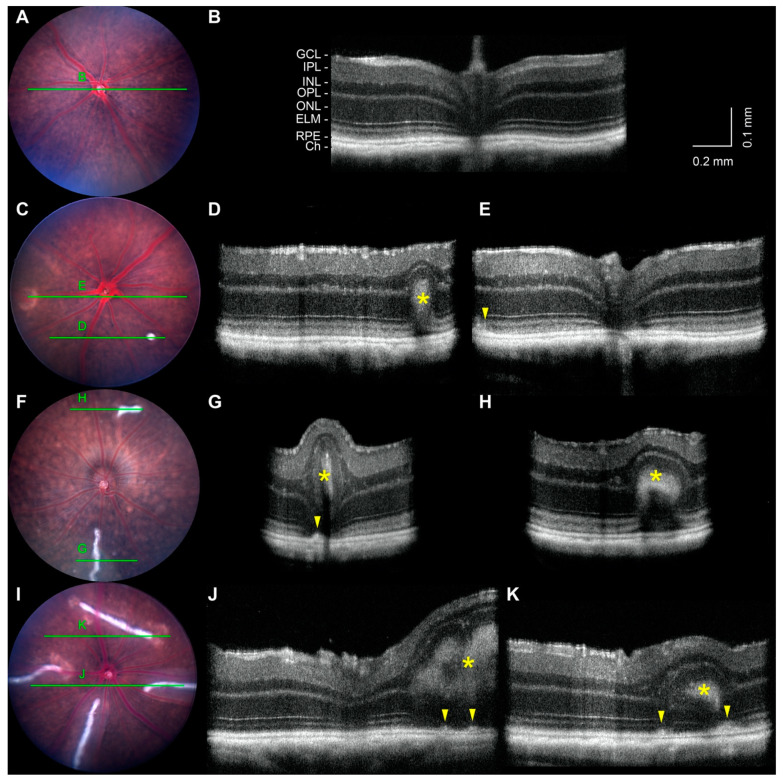

Noninvasive imaging was performed to characterize the posterior ocular defects. In agreement with indirect ophthalmoscopy, fundus imaging of B6 (Figure 3A) and tvrm77 mice (Figure 3C,F,I) at 0.9–1.0 months of age confirmed the absence of white-line lesions in control eyes (0%; 0/11 eyes from 4 F and 7 M mice) and their presence in tvrm77 eyes (48%; 20/42 eyes, 12 F and 16 M mice). The association of lesions in fundus images of one or both eyes (12/28) with the tvrm77 genotype was statistically significant (chi-square test, p = 9.1 × 10−3). Lesions ranged in number from one to five among fundus images of 20 affected eyes of 6 F and 10 M mice and varied in length from small dots to lines occupying more than a third of the diameter of the fundus image (Figure 3C,F,I). Hypopigmented patches were absent in fundus images of B6 control mice (0/11, 4 F and 7 M mice) but present in 64% of images of tvrm77 eyes (27/42, 12 F and 16 M mice). The association of hypopigmented patches in one or both eyes (19/28) with the tvrm77 genotype was also statistically significant (chi-square test, p = 1.4 × 10−4). These lesions typically feature a bright border surrounding darker islands (Figure 3C,I; Figure 1C,D), typical of focal RPE changes at neovascular lesions, as characterized by fundus imaging in other mouse models [42,43,44]. Hypopigmented patches were often observed near white-line lesions (Figure 3I).

Figure 3.

Non-invasive imaging of white-line lesions at 1 month of age. (A) Bright-field fundus image of a B6 eye. (B) B-scan taken from an OCT volume dataset of the same eye. The full OCT dataset is presented in Video S1. GCL, ganglion cell layer; IPL, inner plexiform layer; INL, inner nuclear layer; OPL, outer plexiform layer; ONL, outer nuclear layer; RPE, retinal pigmented epithelium; Ch, choroid. (C,F,I) Fundus images of tvrm77 eyes showing white-line lesions of different sizes. Green lines mark the locations of the corresponding OCT B-scans. (D,E,G,H,J,K) B-scans taken from OCT volume datasets of the same eyes. The full OCT volume datasets are presented in Videos S2–S4. Lesion hyperreflective cores (asterisks) and thickening of the RPE (arrowheads) are indicated. Fundus images were scaled and aligned with the corresponding en face OCT datasets using Fiji. The vertical dimension of the OCT images was increased two-fold to enhance image detail. Scale bar in (B) applies to (D,E,G,H,J,K).

OCT was also performed on the eyes of B6 and tvrm77 mice at 0.9–1.0 months of age, including some of the same eyes assessed by bright-field fundus imaging (Figure 3). Eyes of B6 mice exhibited a normal fundus appearance (Figure 3A) and normal retinal lamination by OCT (Figure 3B, Video S1). Among affected tvrm77 mice, the shortest dot-like white-line lesions (Figure 3C) appeared as a hyperreflective intrusion into the outer retina, with minimal effect on total retinal thickness (Figure 3D, asterisk; Video S2). A thinned outer nuclear layer was detected above the hyperreflective region, and the outer plexiform and inner nuclear layers (OPL and INL, respectively) were distorted above it. A hyporeflective gap was observed at the base of the lesion. Focal RPE thickening was observed near hypopigmented patches, consistent with the OCT appearance of RPE alterations known to accompany retinal neovascular structures [45,46,47]. In longer white-line lesions (Figure 3F,I), a hyperreflective core was observed by OCT (Figure 3G,H,J,K, asterisks; Videos S3 and S4), but the distortion of retinal layers and local increase in total retinal thickness was more pronounced than that associated with dot-like lesions. Focal thickening of the RPE layer was observed in the largest lesions (Figure 3H,J,K, arrowheads), often occurring in the same region as the hypopigmented lesions detected by brightfield fundus imaging (compare Figure 3I,K). In the largest lesions, a thinned ONL appeared both below and above the hyperreflective core along much of its length (Figure 3G,H,J,K, asterisks; Videos S3 and S4), although at some locations, the ONL was interrupted and the hyperreflective core extended from the OPL toward the outer retina (Figure 3K).

We searched the literature for retinal lesions resembling the white-line lesions, particularly as characterized by OCT. Outer and full-thickness retinal folds that develop as a complication of rhegmatogenous retinal detachment surgery [48] appear as pale linear features by color fundus imaging and corresponding hyperreflective intrusions by OCT, which distend the overlying retinal layers and cause a local increase in total retinal thickness [49,50,51]. Retinal folds with similar color fundus imaging and OCT features are also found in inherited forms of canine retinal dysplasia [52]. Our phenotypic observations suggest that the white-line lesions in tvrm77 mice are retinal folds.